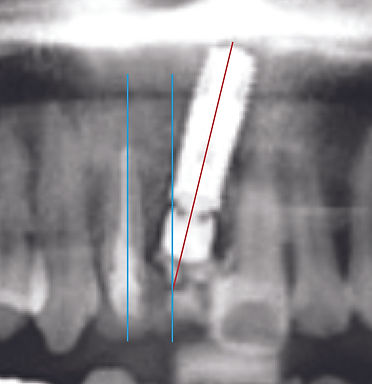

임플란트 위치, 시술 후 수복 될 최종치아의 형태를 계획한 그대로

1mm 오차도 허용하지 않는 수술 결과로 치아의 기능과 심미성을 보장합니다!

기존 임플란트 시술

임플란트의 식립 위치가 올바르지 않을 경우 교합력(음식물을 씹는 힘)을 지탱하지 못해,

주변 뼈 손실, 주의 치주염을 유발하여 임플란트 수명이 단축됨

디지털 임플란트 R2GATE 시술

계획에 의한 정확한 식립으로 과도한 교합합 또는 비정상적인 외부압력으로부터

임플란트를 보호하여 보다 오래도록 사용할 수 있음